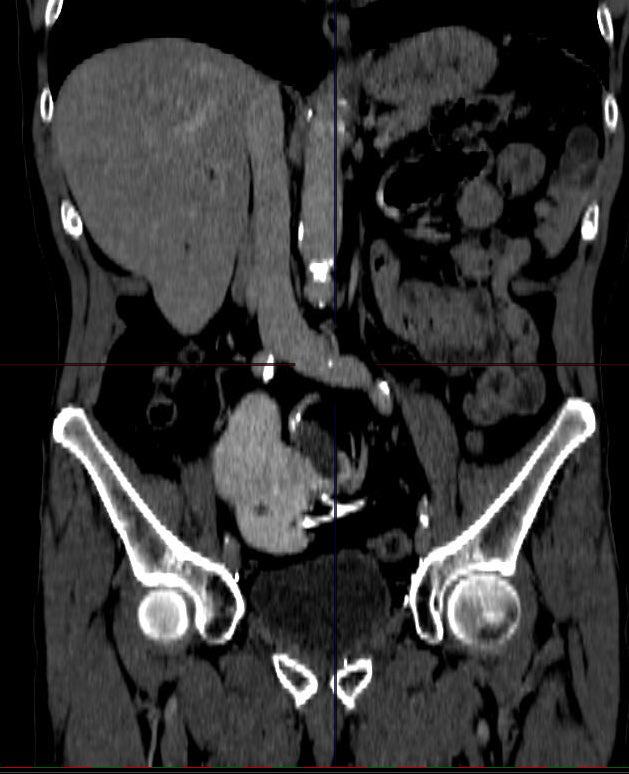

Guido Giusti

Guido Giusti@GuidoGiusti·

Never underestimate even a small stone …. This is what can happen! It is always impressive 2c such a morbid evolution! And believe surgery was not a piece of cake .. inflammatory infiltration of both liver and cava! 🥲😱#ETCE